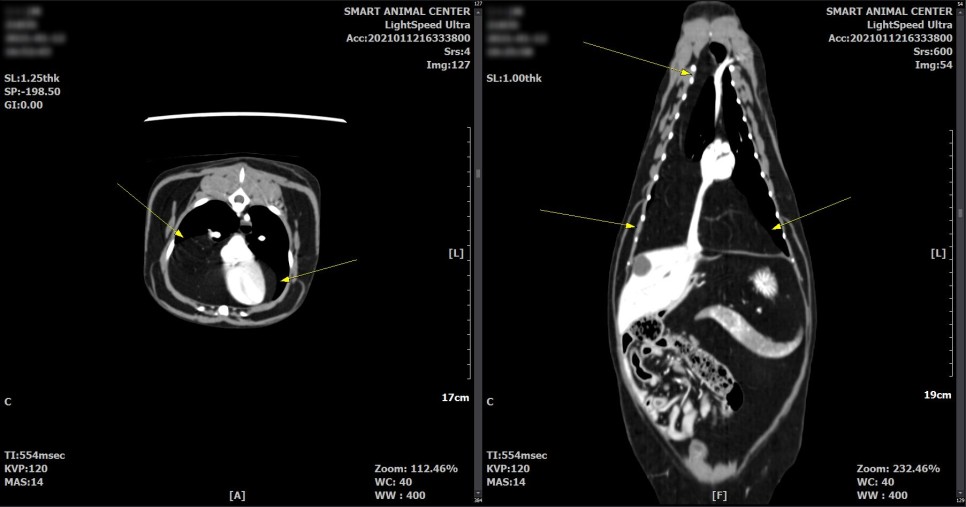

CT 검사 결과

횡격막의 일부 결손 부위와 흉강 내 다량의 지방 병변이 확인되었습니다.

횡격막 결손부에 의한 다량의 지방 디스크가 있을 수 있으며,

또한 영상학적으로 악성도를 지시하는 것과 같은 소견은 관찰되지 않았습니다.

다량의 지방으로 폐 실질 등, 왼쪽 변위가 유발되고 있다고 판단되었습니다.